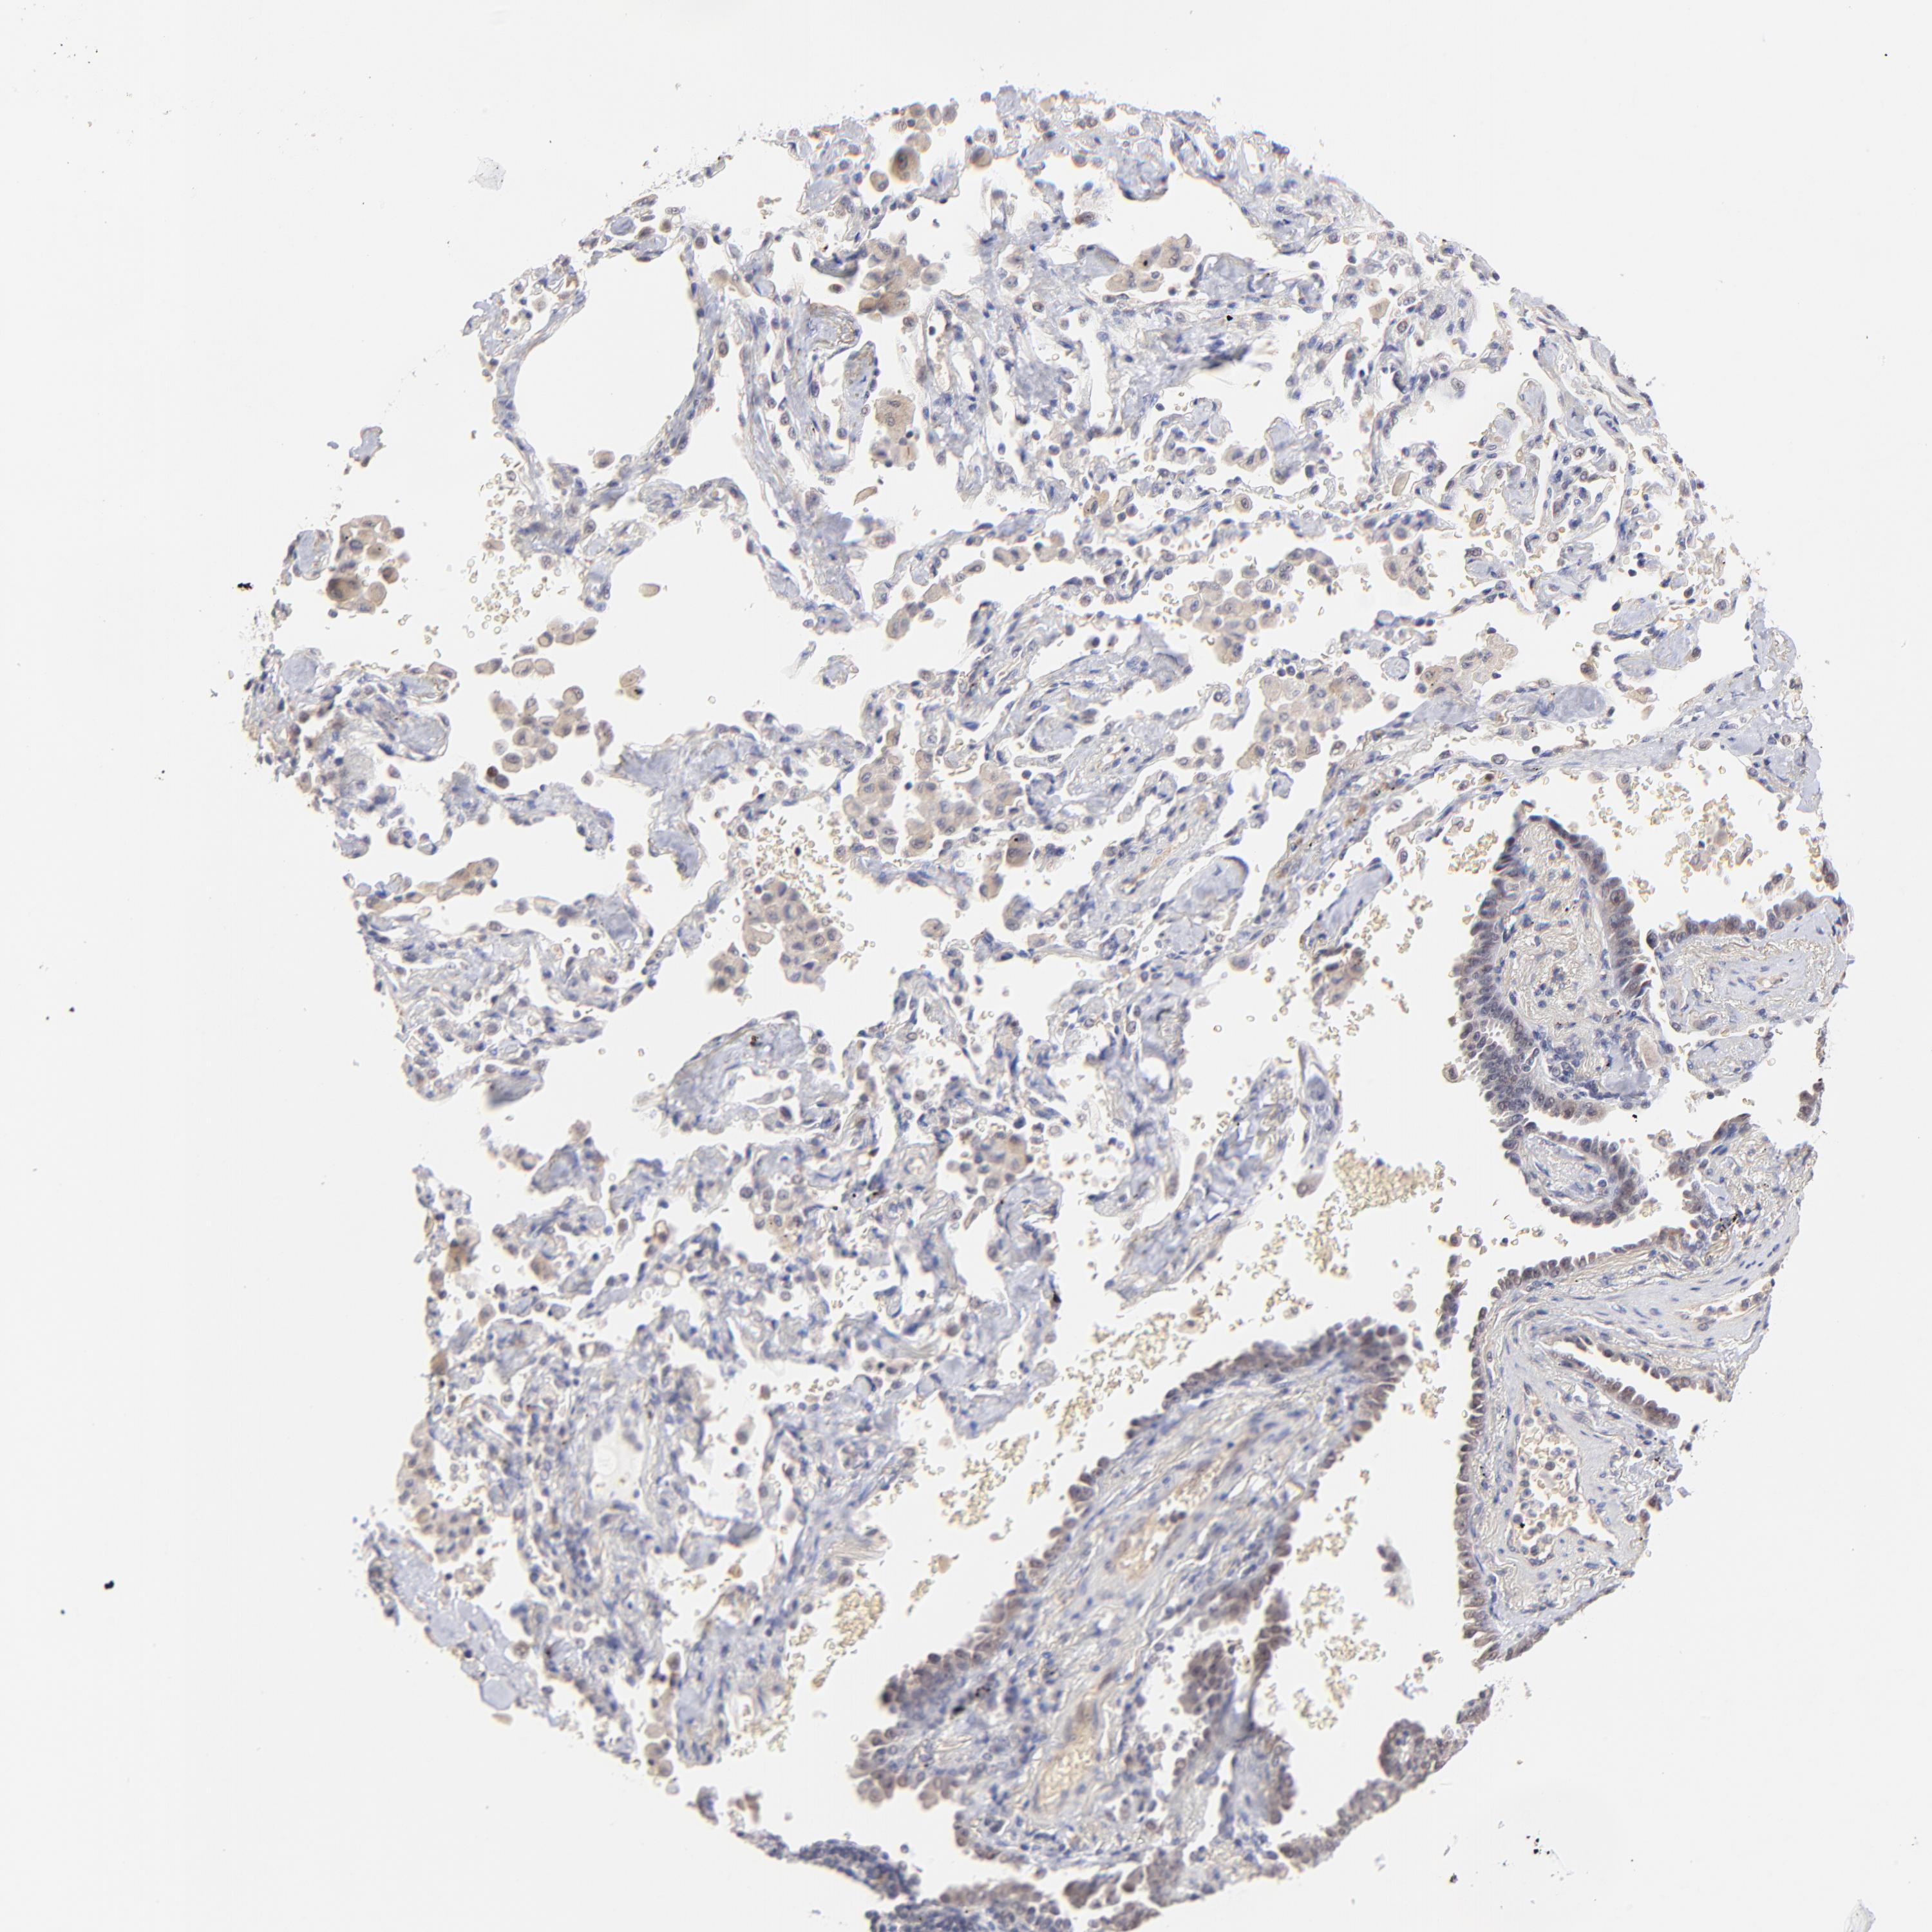

CANCER LUNG CANCER Show tissue menu

Lung cancer

Human cancer

Lung adenocarcinoma

Lung squamous cell carcinoma